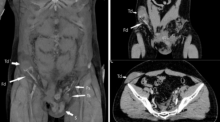

Begini Kronologi Pria Alami Testis Masuk Perut akibat Kecelakaan Tragis Kesehatan - 14 Oct 2023, 20:10